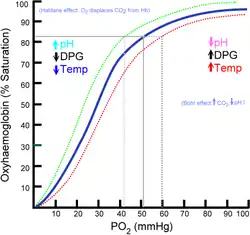

In medicine, oxygen saturation, commonly referred to as "sats", measures the percentage of hemoglobin binding sites in the bloodstream occupied by oxygen.[3]: 370 At low partial pressures of oxygen, most hemoglobin is deoxygenated. At around 90% (the value varies according to the clinical context) oxygen saturation increases according to an oxygen-hemoglobin dissociation curve and approaches 100% at partial oxygen pressures of >11 kPa. A pulse oximeter relies on the light absorption characteristics of saturated hemoglobin to give an indication of oxygen saturation.[4]

An SaO2 (arterial oxygen saturation) value below 90% causes hypoxia (which can also be caused by anemia). Hypoxia due to low SaO2 is indicated by cyanosis, but oxygen saturation does not directly reflect tissue oxygenation. The affinity of hemoglobin to oxygen may impair or enhance oxygen release at the tissue level. Oxygen is more readily released to the tissues (i.e., hemoglobin has a lower affinity for oxygen) when pH is decreased, body temperature is increased, arterial partial pressure of carbon dioxide (PaCO2) is increased, and 2,3-DPG levels (a byproduct of glucose metabolism also found in stored blood products) are increased. When the hemoglobin has greater affinity for oxygen, less is available to the tissues. Conditions such as increased pH, decreased temperature, decreased PaCO2, and decreased 2,3-DPG will increase oxygen binding to the hemoglobin and limit its release to the tissue.[12]